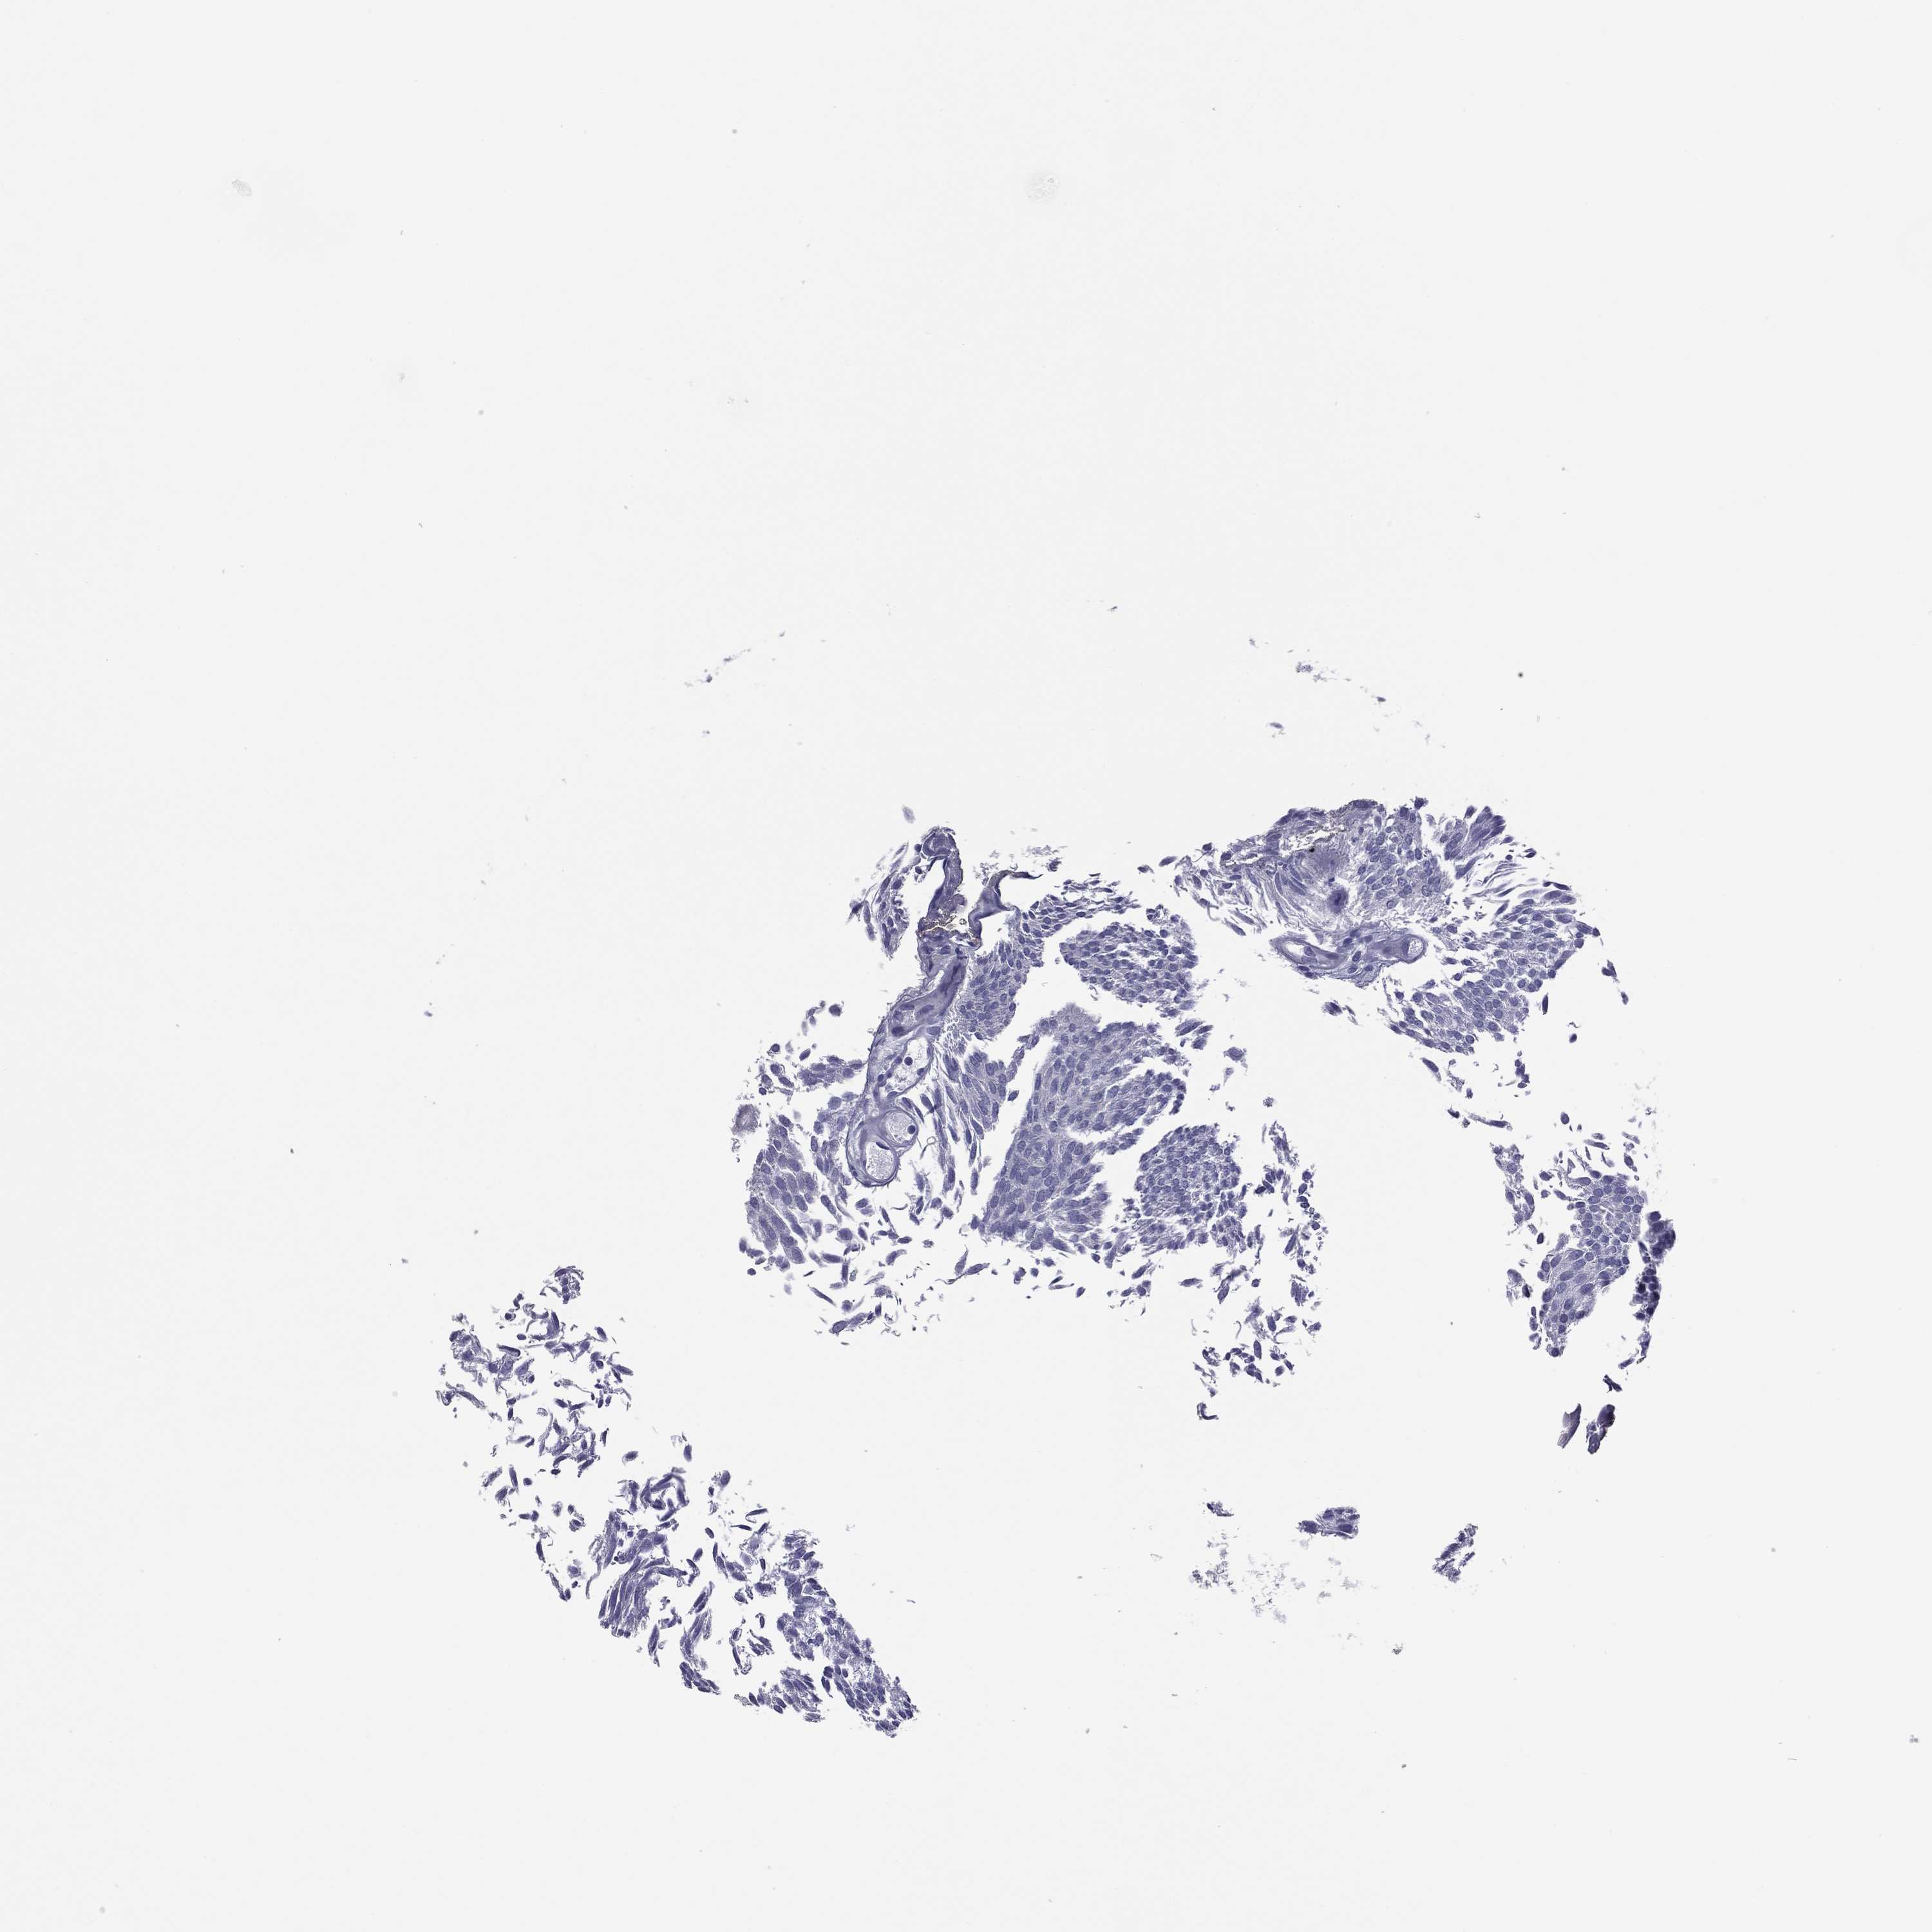

UROTHELIAL CANCER - Protein expressioni

A mouse-over function shows sample information and annotation data. Click on an image to view it in a full screen mode. Samples can be filtered based on level of antibody staining by selecting one or several of the following categories: high, medium, low and not detected. The assay and annotation is described here.

Note that samples used for immunohistochemistry by the Human Protein Atlas do not correspond to samples in the TCGA dataset.

Antibody stainingi

Antibody staining in the annotated cell types in the current human tissue is reported as not detected, low, medium, or high, based on conventional immunohistochemistry profiling in selected tissues. This score is based on the combination of the staining intensity and fraction of stained cells.

Each image is clickable and will lead to virtual microscopy that enables deeper exploration of all samples and also displays staining intensity scores, fraction scores and subcellular localization as well as patient and tissue information for each sample.

Antibody HPA077615

Staining

High

Medium

Low

Not detected

Intensity

Strong

Moderate

Weak

Negative

Quantity

>75%

75%-25%

<25%

None

Location

Nuclear

Cytoplasmic/membranous

Cytoplasmic/membranous,nuclear

Urothelial carcinoma, High grade

Urothelial carcinoma, Low grade